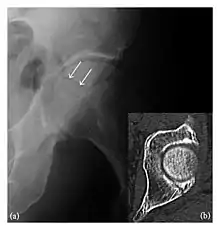

Proximal femoral fractures usually occur in osteoporotic patients, and their signs include subtle neck angulation, trabecular angulation, and subcapital impaction line. A frog-leg lateral view may be helpful if the greater trochanter is short enough. However, positioning can be difficult because of hip pain. In patients with strong suspicion of proximal femoral fracture and negative radiographs, MRI limited to coronal T1 W images and scintigraphy can be highly valuable (Figures 13 and 14). Such an option, with limited examination time, is cost-effective and allows reliable exclusion or confirmation of the diagnosis, preventing an unnecessary stay at the hospital or delayed treatment. Moreover, MRI helps to detect soft tissue abnormalities which are more frequently seen in femoral, acetabular, and pubic injuries than sacral lesions. Concomitant fractures are also frequently seen in typical pelvic sites.[1]

a

b

Figure 13: Partial osseous avulsion of the gluteal muscles at the greater trochanter in a 59-year-old man who presented with the right hip pain without a history of trauma. Lauenstein view and anteroposterior and radiographs (not shown) did not show an obvious fracture line or disruption of bony contours in the acetabulum or the right femoral neck. (a) Coronal T1-weighted MRI displays an incomplete fracture line extending partially from the greater trochanter (arrow). (b) Coronal short tau inversion recovery MRI shows heterogeneous hyperintensity in the same region (arrow) as well as hyperintensity within the gluteus medius and minimus muscles (arrowheads) consistent with tissue edema and hematoma.[1]

Figure 14: Subcapital insufficiency fracture in a 55-year-old man with a left hip pain without a history of trauma. Anteroposterior and Lauenstein view radiographs centered on the left hip do not show an obvious fracture line, but mild acetabular osteophytosis was noted consistent with hip osteoarthritis (not shown). (a) Coronal T1-weighted MRI shows a linear low-signal band through the femoral neck corresponding to a fracture line (arrowheads). (b) Bone scintigraphy shows focal uptake (arrow) corresponding to the fracture.[1]